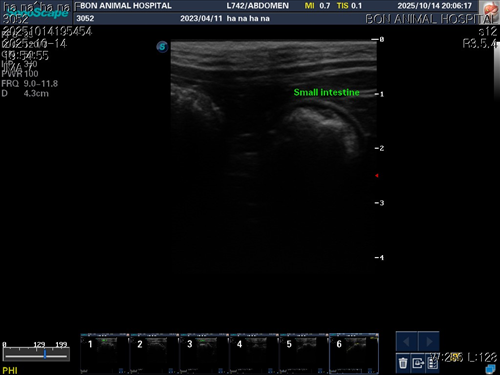

10월 10일 포도를 토해논후로 식욕저하 기력저하가 있어서 동물병원에 방문해서 엑스레이를 찍었는데 우선 지켜보자는 말과 소화제처방과 주사를 맞고 집왔습니다 그 후로도 안먹어서 12일에 동물병원에가서 혈액검사도 하고 수액도 맞았습니다 췌장쪽 수치가 좀 높아서 췌장쪽만 다시 검사했는데 수치는 괜찮았습니다 식욕촉진이랑 소화제처방 받아서 먹이는데 식욕저하도 여전하고 기력이 좀 없고 10일부터 14일까지 대변을 못보고있어서 14일에 병원에 가서 엑스레이랑 초음파를 했는데 장폐색일수도 있다는 말을 들었습니다 초음파상으로는 소장쪽 이물이 의심된다고 하셨어요ㅠ